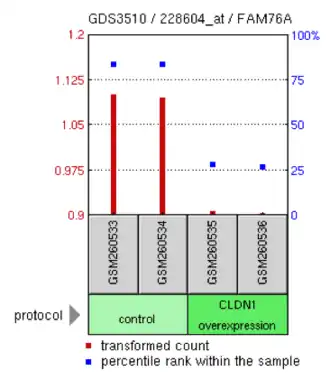

Experimental data

Select data from three experiments involving FAM76A are shown below. In one experiment, CLDN1 over-expression in lung adenocarcinoma cells decreased FAM76A expression.[19] In another experiment, androgen insensitive prostate cancer cells were shown to have reduced expression of FAM76A compared to androgen sensitive cells.[20] Another experiment demonstrated that metaphase II oocyte cells were shown to have more expression of FAM76A compared to control cells.[21]

- Selected NCBI Geo Data

-

FAM76A levels in H. sapiens lung adenocarcinoma cell lines were compared between cultures that had claudin-1 (CLDN1) overexpression and control cells

FAM76A levels in H. sapiens lung adenocarcinoma cell lines were compared between cultures that had claudin-1 (CLDN1) overexpression and control cells -